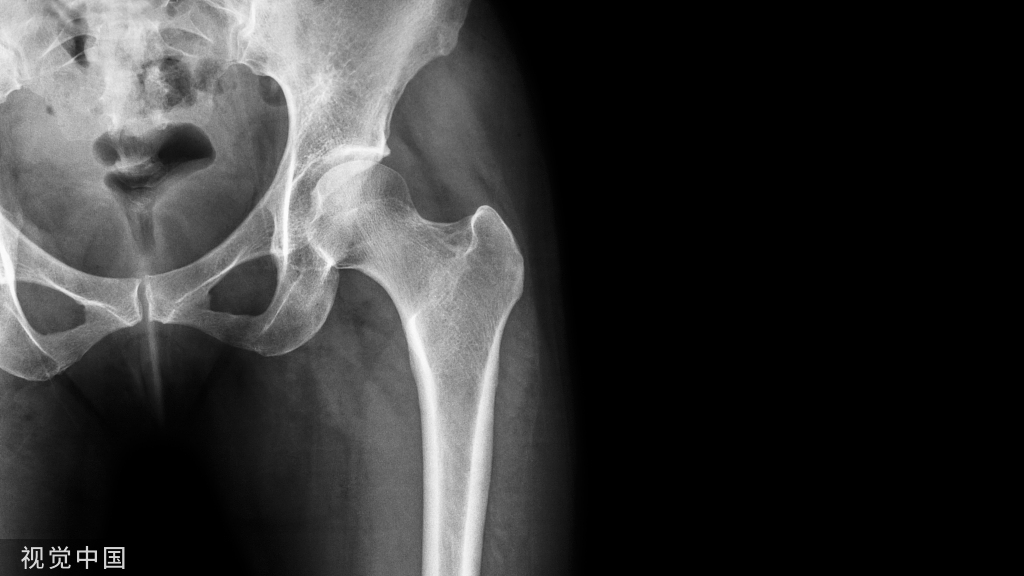

辛迪思的LCP产品:髋